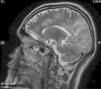

Se efectuó resonancia magnética por imágenes (RMI) con contraste en la que se observó extensa lesión subcortical en lóbulo frontal, parietal y occipital izquierdos, con extensión al esplenio del cuerpo calloso y mesencéfalo superior del lado izquierdo, y compromiso de los lóbulos parietal y occipital derechos. Las imágenes predominaban en lóbulos posteriores y dibujaban las fibras subcorticales en «U». No hubo realce con el contraste IV, ni efecto de masa sobre estructuras adyacentes de la línea media (figs. 1-5).

El VJC se reactiva ante cuadros de inmunosupresión grave, e induce la infección lítica de los oligodendrocitos con lesiones multifocales de desmielinización. La enfermedad tiene una prevalencia del 1 al 4% entre los pacientes con sida. El curso clínico es progresivo y con déficit neurológico focal en el 80% de los pacientes afectados. El examen del LCR es normal o con alteraciones inespecíficas, (hiperproteinorraquia moderada y pleocitorraquia mononuclear)4. La RM muestra la presencia de lesiones, por lo general bilaterales, simétricas o asimétricas, con predominio en lóbulos parieto-occipitales, bien delimitadas y localizadas en áreas periventriculares y en la sustancia blanca subcortical. Pueden ser únicas o múltiples, no refuerzan con el contraste, no están rodeadas de edema, ni producen efecto de masa, y dibujan las fibras subcorticales en «U» o fibras arcuatas; un tercio de los pacientes tienen compromiso de la fosa posterior. Entre un 5-10% de los casos, esta última localización se revela como la única manifestación de la enfermedad4. El diagnóstico se confirma por la PCR en el LCR. La sensibilidad de la prueba es variable (40-80%), posee una alta especificidad (mayor del 90%) y un valor predictivo positivo del 100%5.